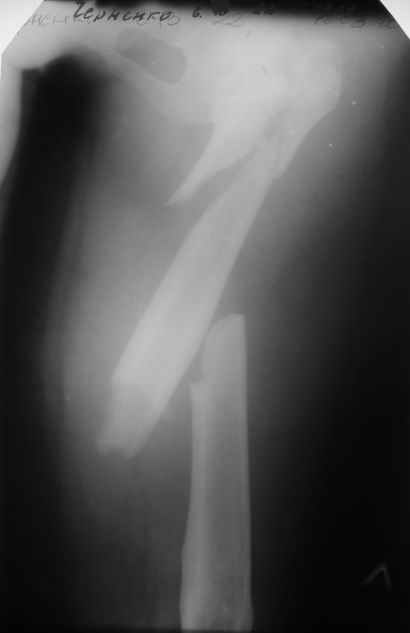

Пациентка 23 лет, доставлена в клинику с Диагнозом: Закрытый сегментарный оскольчатый перелом левой бедренной кости в верхней и средней трети. Травма в результате ДТП 10.03.2006г. Из анамнеза у пациентки диспластический левосторонний коксартроз, S-образный сколиоз 2ст. В 1999г в Кургане выполнялась остеотомия бедра в нижней трети и коррекция укорочения конечности на 3 см (рентгенограммы бедра и таза до травмы в приложении). До получения травмы пациентка ходила без боли с полной нагрузкой на левую ногу. Учитывая дисплазию левого ТБС, пациентке, вероятно, предстоит операция тотального эндопротезирования лев ТБС, что требует анатомичного восстановления проксимальногоотдела бедра. Рассматриваются следующие вариант остеосинтеза:1) Экстракортикальный остеосинтез проксимального и дистального перелома пластиной с угловой стабильностью типа LISS( г Рыбинск); 2) Ретроградный интрамедуллярный блокированный остеосинтез дистального перелома и накостный синтез проксимального пластиной с угловойстабильностью; 3) Остеосинтез бедра в аппарате внешней фиксации с фиксацией таза и возможной открытой адаптацией фрагментов. Хотелось бы узнать Ваше мнение. С уважением Украинский Евгений, г.Краснодар, ККБ N1, ТОО N3.

Судя по снимкам до перелома, большой вертел располагался высоковато. Может, подумать о том, чтобы при остеосинтезе его переместить дистальнее и/или латеральнее? Что скажут коллеги, активно занимающиеся эндопротезированием?

Ма бы наложили спицевой дистрактор (1 спица в крыло спереди назад, другая в дистальный метафиз бедра), две дуги, три телескопических стержня. Дистракция в приведении. Во фрагмент большого вертела, видимо, понадобится отдельная спица и отдельная дуга, за которую руками вертел подправить в желаемое положение, диафикировать спицами по заднему контуру отломков и шейки, чтобы не мешали проведению гвоздя потом.